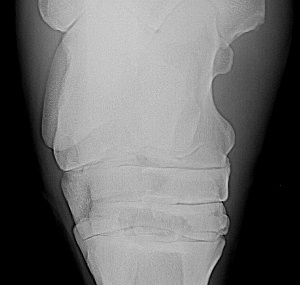

Dr. O. - here is another x-ray (I seem to need to do separate posts):

Leg #2

An addendum to the above. I have moved the radiograph images to a larger screen and viewing them it appears all the fragments are off the back of the talus and may communicate with the talocaneal joint (correction off the back of the calcaneus and communicates with the talocrural joint~DrO) cand have minimal effect on the stability of the joint. Does the veterinarian who has the originals agree?

Well, Janice you do help buy baby a new pair of shoes but I have to correct my anatomy above, this is most likely off the calcaneus and not the talus and communicates with the talocrural joint not the talocalcaneal joint by way of the proximal intertarsal joint. I must of had talus on the brain. The gist of my comments on prognosis and treatment still apply. I do think a flexed lateral and flexed dorsolateral-posteriomedial and a skyline view of the plantar surface of the talus would further eludicate whether the 4th tarsal bone is involved or intraarticular bone is involved.